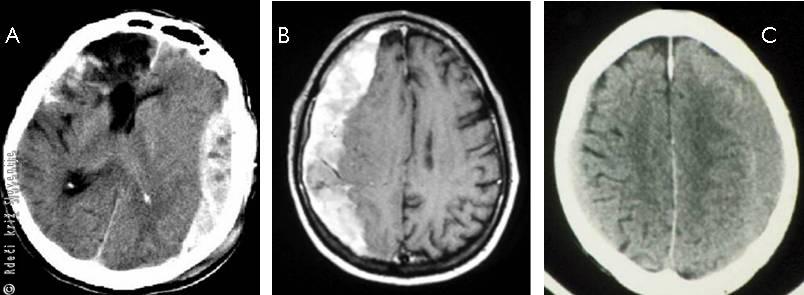

Slika 14

A – Subduralna krvavitev (izliv krvi pod trdo možgansko opno - računalniška tomografija sveže krvavitve.

B – Nekaj dni stara krvavitev.

C – Kronična krvavitev